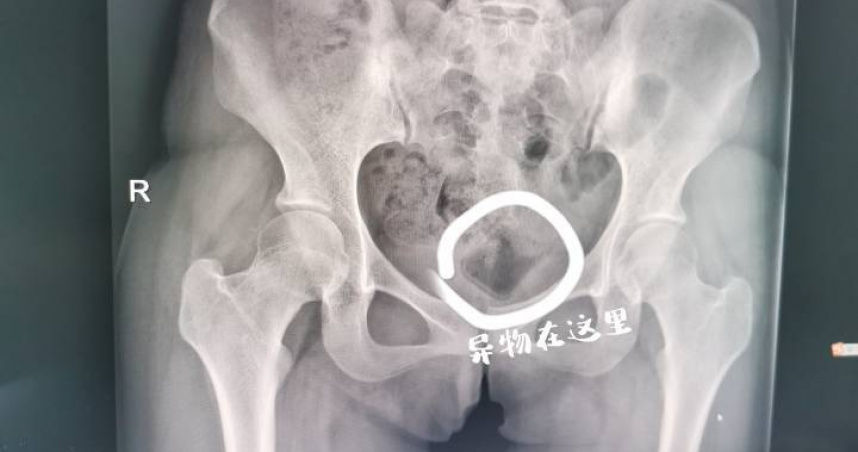

雖然閨房情趣能增進情侶或夫妻間的感情,但若沒有拿捏好分寸,恐怕只會帶來反效果。大陸浙江省杭州市一名女大生近日到醫院求診,害羞地喊著下體疼痛;經醫師詢問,才得知原來患者和男友追求刺激,竟把異物塞進下體,事後怎麼拿也拿不出來,但又不好意思就醫,直到痛到無法走路,才到婦產科尋求協助。

《錢江晚報》報導,19歲的小楊(化名)是名大學生,不久前交了男友,2人為了尋求刺激,竟將異物塞進下體。由於缺乏醫學常識,再加上心裡窘迫,小楊覺得這件事難以啟齒,一直沒到醫院檢查,也沒有告訴其他人,直到1個月後下體開始飄出異味,且疼痛難耐,才在朋友陪同下到杭州市西溪醫院婦產科就診。

醫生檢查發現,小楊的陰道深處的確有異物,該物體光滑且無著力點,憑普通醫療器械工具無法取出。高建松醫師表示,雖然異物在體內停留的時間長,所幸位置不算深,於是在超音波的引導下,經過多次探查,最後終於用手術鉗取出了小楊體內的異物,原來是個長5公分寬3公分、類似化妝品蓋子的東西。

高醫師透露,異物在體內已經引起了發炎反應,還好及時取出來,如果再不取出來,折磨人不說,還會引起感染,對未來生育方面都會有影響。醫師提醒,女性平時除了應該注意衛生,規律生活,不要追求這種刺激,如果有身體不適,應該及時到醫院尋求醫護人員的幫助,否則後果恐不堪設想。